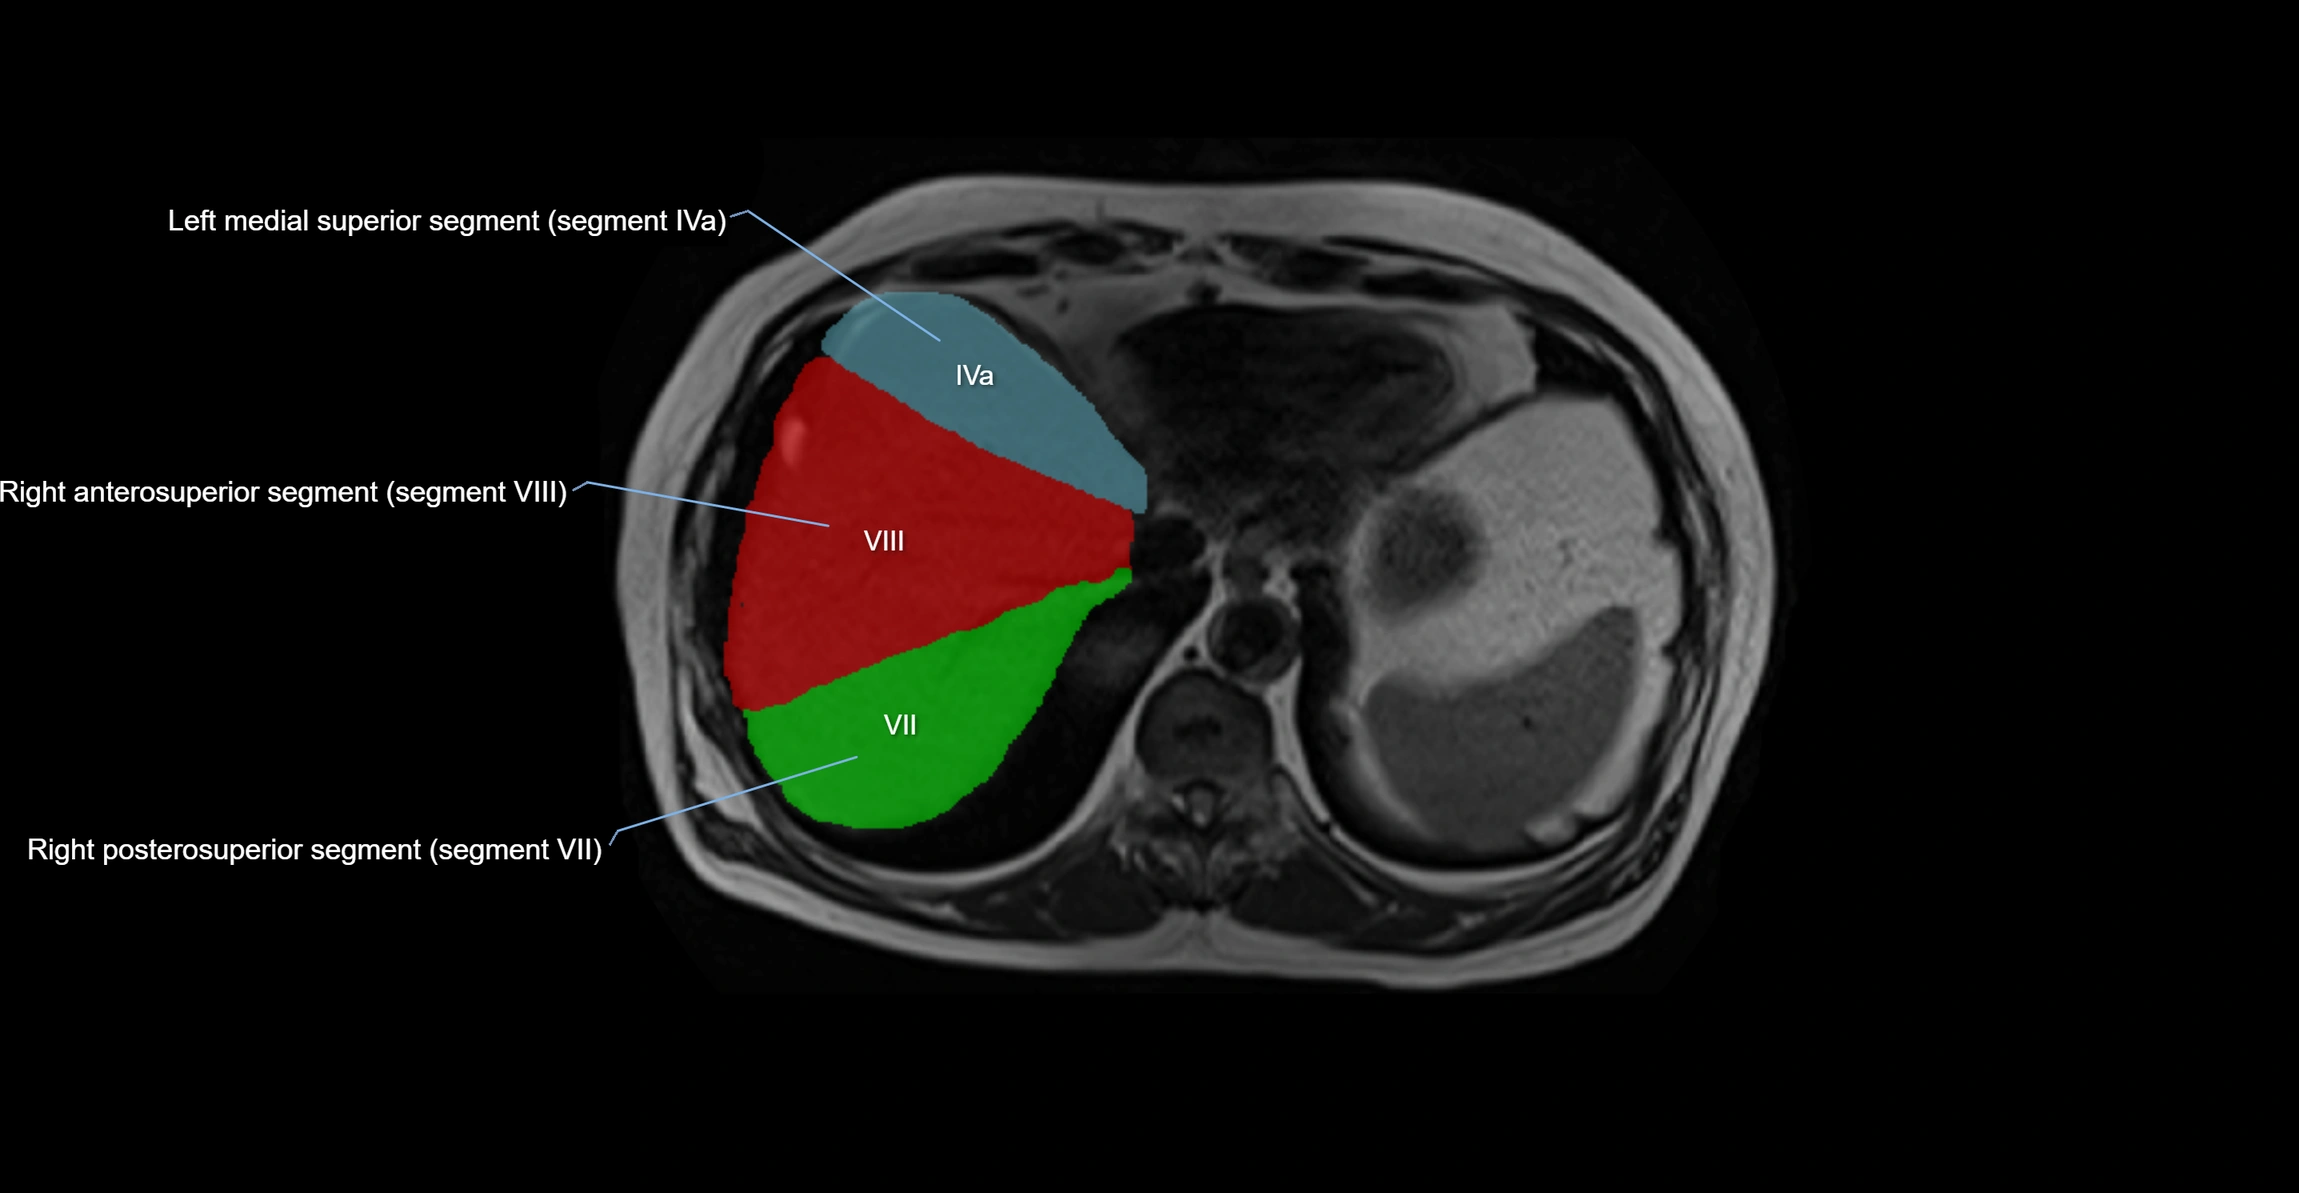

MRI Appearance

T1-weighted images:

• Parenchyma shows intermediate signal intensity, similar to rest of liver

• Lesions (tumors, fat, fibrosis) show altered signal compared to background liver

T2-weighted images:

• Normal parenchyma shows intermediate to slightly hyperintense signal

• Pathologies (cysts, hemangiomas, tumors) demonstrate variable high signal

STIR:

• Suppresses fat, highlighting edema, inflammation, or lesion signal

• Useful in detecting caudate lobe hypertrophy in cirrhosis

T1 Fat-Saturated (Pre-contrast):

• Caudate lobe appears as intermediate signal parenchyma against suppressed fat

T1 Fat-Saturated Post-Contrast (Gadolinium):

• Homogeneous enhancement in normal parenchyma during portal venous phase

• Lesions (HCC, metastasis, hemangiomas) enhance with characteristic dynamic patterns

• Important in detecting vascular invasion and caudate hypertrophy